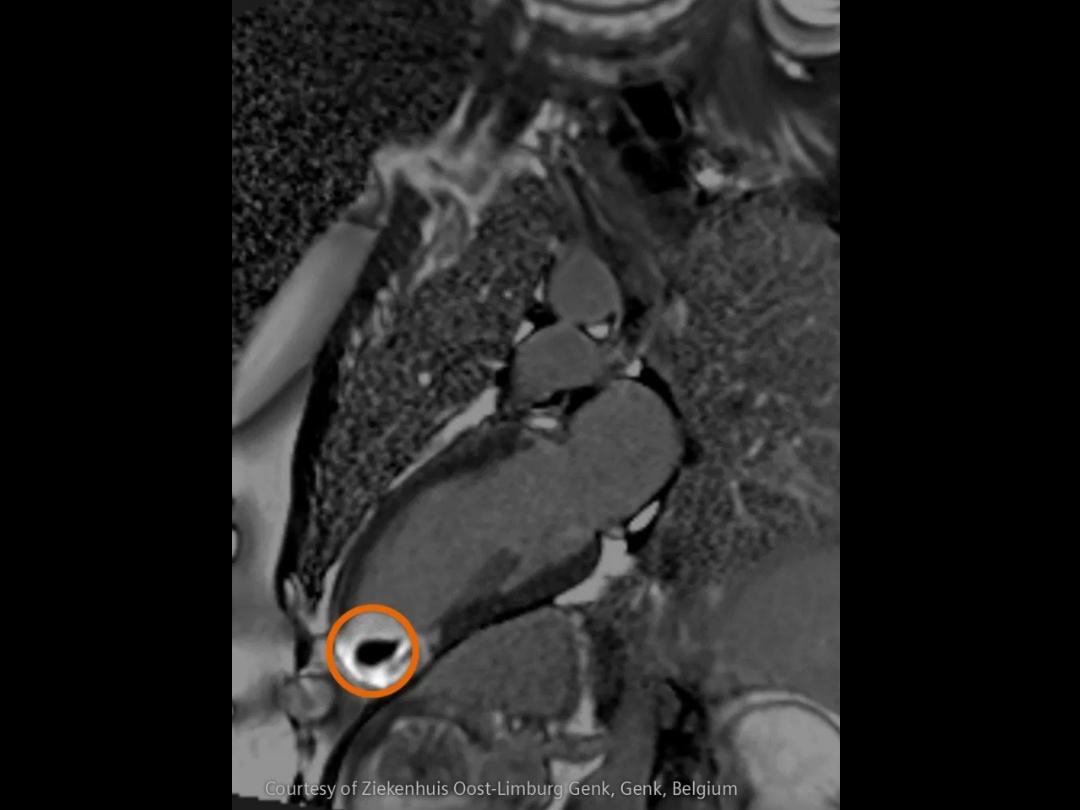

In stroke care, time is brain. Rapid and accurate imaging is crucial to assess the extent of brain injury and guide immediate treatment. Angiography, MRI, CT, ultrasound, and lab diagnostics are essential tools in identifying stroke type, location, and severity. Advances in imaging technology now allow for even faster acquisition, improved resolution, and enhanced visualization of brain tissue and blood vessels. Innovations such as perfusion imaging, real-time vascular mapping, and AI-assisted diagnostics are transforming stroke workflows and enabling precise, timely interventions.